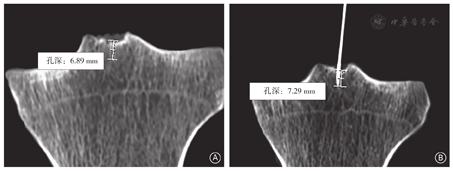

50例胫骨平台实物证明孔道存在(图2)。孔口与关节腔仅存在1层厚度约1 mm膜组织间隔,壁及底均为骨松质,解剖实物见孔口呈圆形,孔口直径为(2.0±0.4)mm,孔道深度为(9.1±2.5)mm,中部直径(1.6±0.3)mm,与影像学测量结果相一致。孔道内容物HE染色结果显示为较致密结缔组织及松质骨,未见上皮及滑膜细胞。孔内容物与孔壁并不完全帖附、存在缝隙。

CT引导下在髁间隆突中凹处使用直径≤1 mm的针头可轻易探到孔道,进针深度与孔道深度基本一致。可见孔口位于髁间隆突中凹处、前后叉韧带止点之间,周围区域与骨质仅有一薄膜间隔。HE染色显示孔口周围为软骨,孔道中部孔壁及孔底为松质骨,孔内容物为较致密结缔组织,孔道口覆盖物为滑膜(图3,图4)。